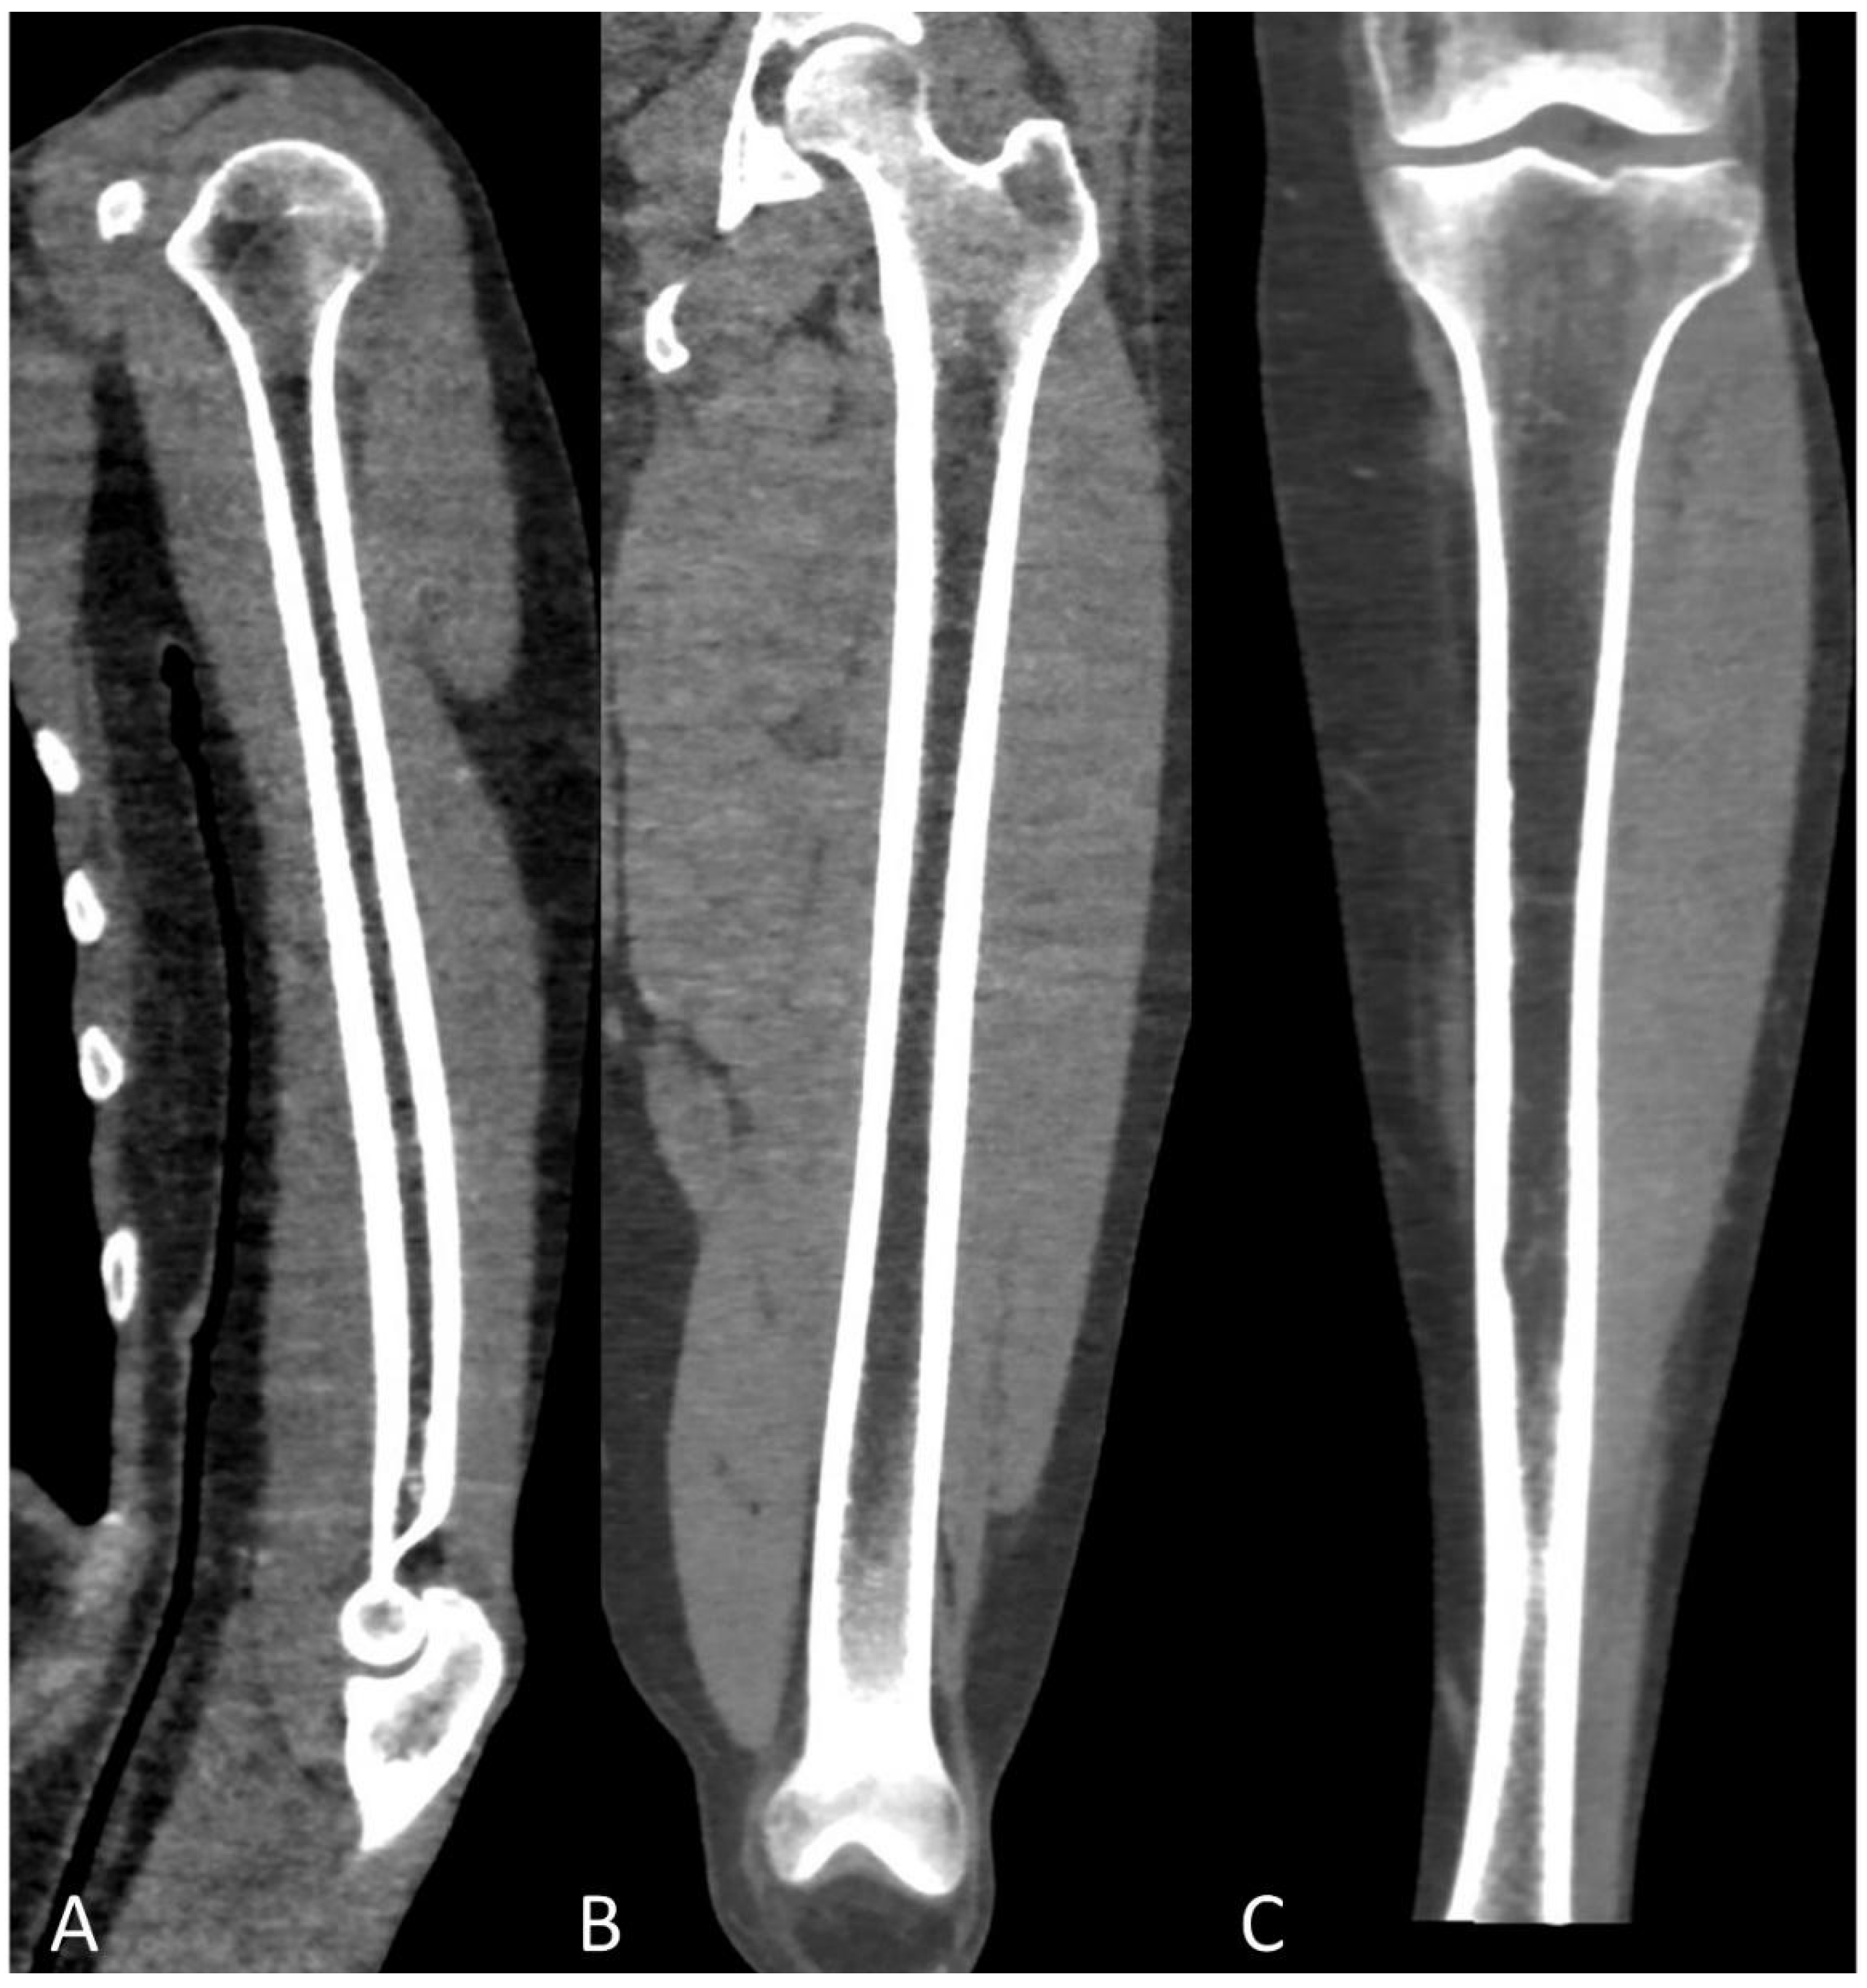

Figure 9.

Multiplanar CT images with “soft tissue” window showing the distinctive aspect of normal (A) humeral, (B) femoral, and (C) tibial fatty bone marrow on low-dose CT in healthy adults.